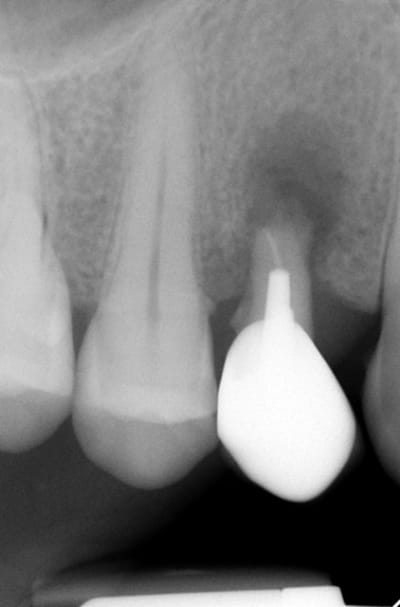

Bonsoir merci pour ta question, comme tu vois sur la radioDVT il n y avait pas assez de place pour mettre un 6,5mm seulement la racine palatinale était d une longueur de 10/12 mm. Mon premier challenge etait d avoir une premiere stabilité supérieure à 40 Ncm.Le laboratoire est donc important pour que le patient puisse nettoyer facilement la région implantaire.

la radioDVT que j ai oublié de poster

L ossintegration est visible surtout en comparant avec la radio au moment de l implantation. Je cherche la photo pour la joindre.